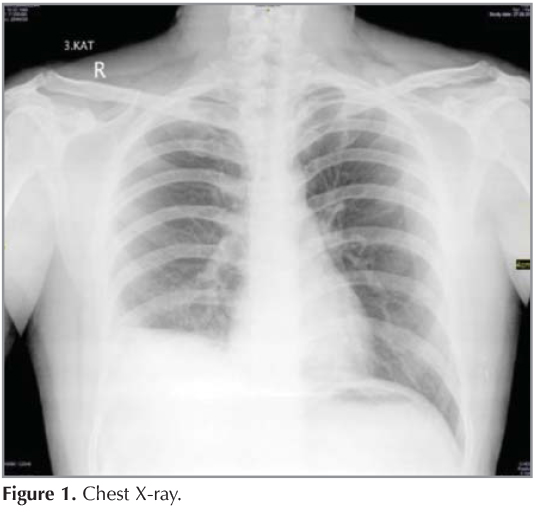

From www.clinmedjournals.org

Is There a Relationship between Serum DDimer Levels and Thorax CT D Dimer Chest X Ray The most common presenting symptom is dyspnea followed by chest pain (classically pleuritic but often dull) and cough. However, it is a useful tool for ruling out other lung pathology (e.g. Cxr findings associated with pe include pleural effusion and/or an area of atelectasis where a small area of lung tissue has collapsed. Known as a computed tomographic pulmonary angiography. D Dimer Chest X Ray.